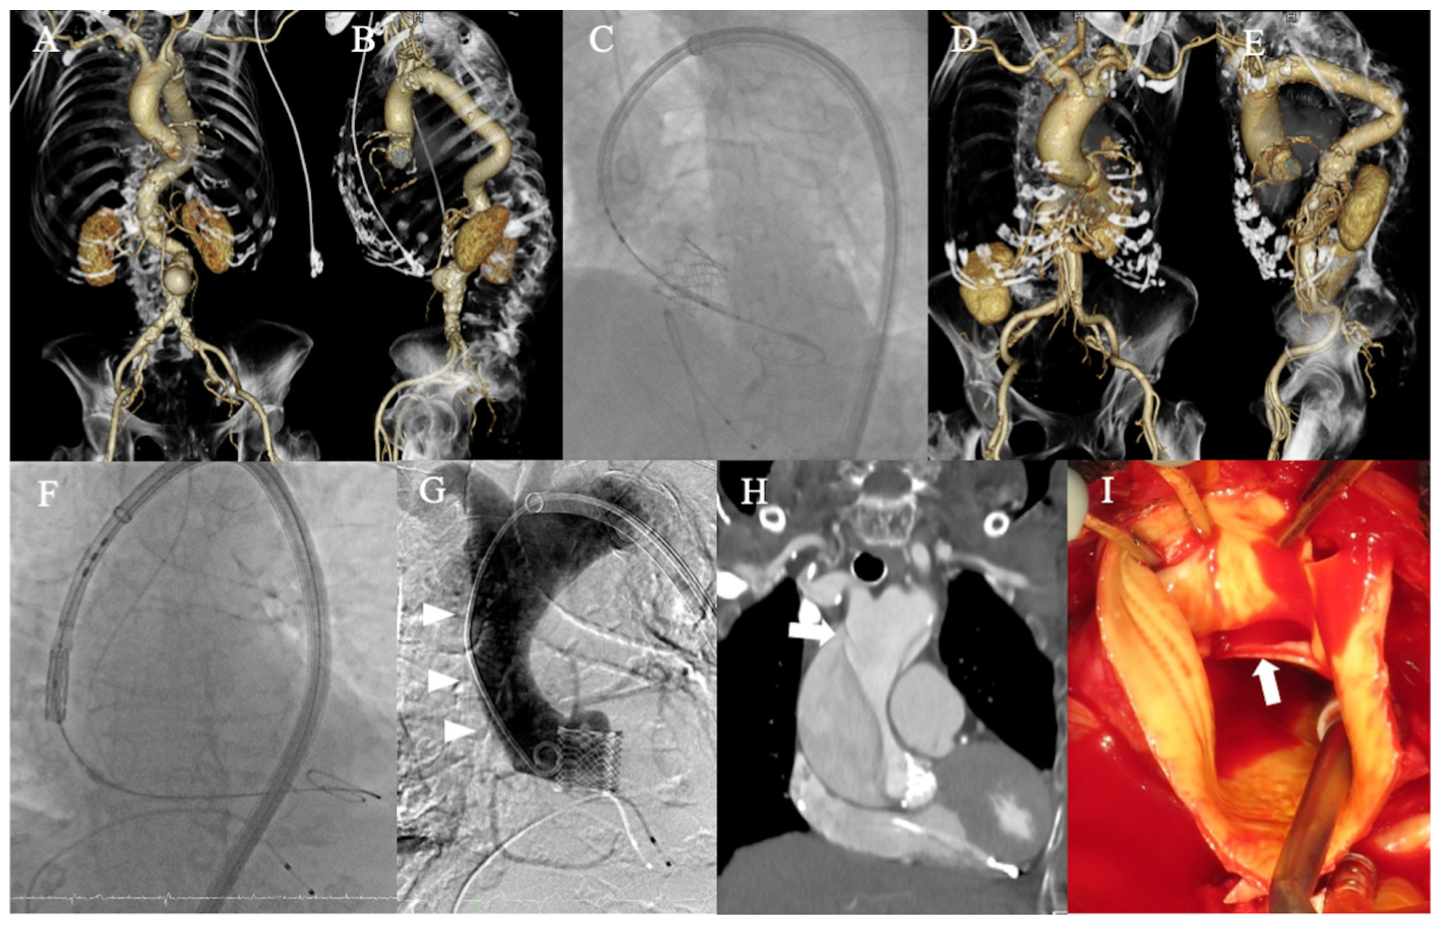

A long-sheath assisted transfemoral transcatheter aortic valve replacement (A-C: case 1; D-I: case 2). (A, B, D, E) Volume-rendering images of the aorta. (C) A successfully implanted valve. (F) Valve deployment. (G, H, I) Ascending aorta dissection (arrowheads) and dissection entry (arrows).

Reprinted with permission from Higuchi R, Nishida K, Saji M, Ohno M, Takamisawa I. J Invasive Cardiol. 2023 Apr;35(4):E221-E222.